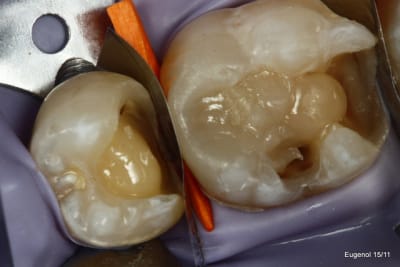

un truc que je fais souvent, quand je monte deux compo volumineux en contact, je monte le plus gros et difficile sans matrice et comme ça j'ai accès a la marge, et je peux donner une jolie forme galbée proximale

puis je monte le suivant avec une seule matrice...

plus facile je trouve d'avoir le point de contact

Ben les photos finales c'est après réglage de l'occlusion sinon c'est pas drôle.

Quand on s'appuie sur les cuspides restantes et qu'on donne une morphologie assez naturelle, en général il y a peu de retouche occlusale.

Sinon je fais les sillons secondaire a la sonde.

C'est du compo Enamel HRI en dentine et Esthelite en email qui se sculpte facilement et reste pourtant souple et autolissant...

Le polissage c'est des brossettes chargées en silice, et avec de la pâte à polir.